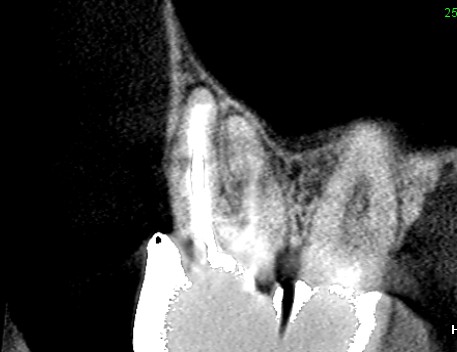

初診時のCT画像です。根管治療不足で根管充填が根の先まで足りていません。

矢印の先が根の先にできている膿です。膿は上顎洞という副鼻腔に接しています。ここから上顎洞に炎症が波及したり、膿が上顎洞にあふれ出てもおかしくない状態です。